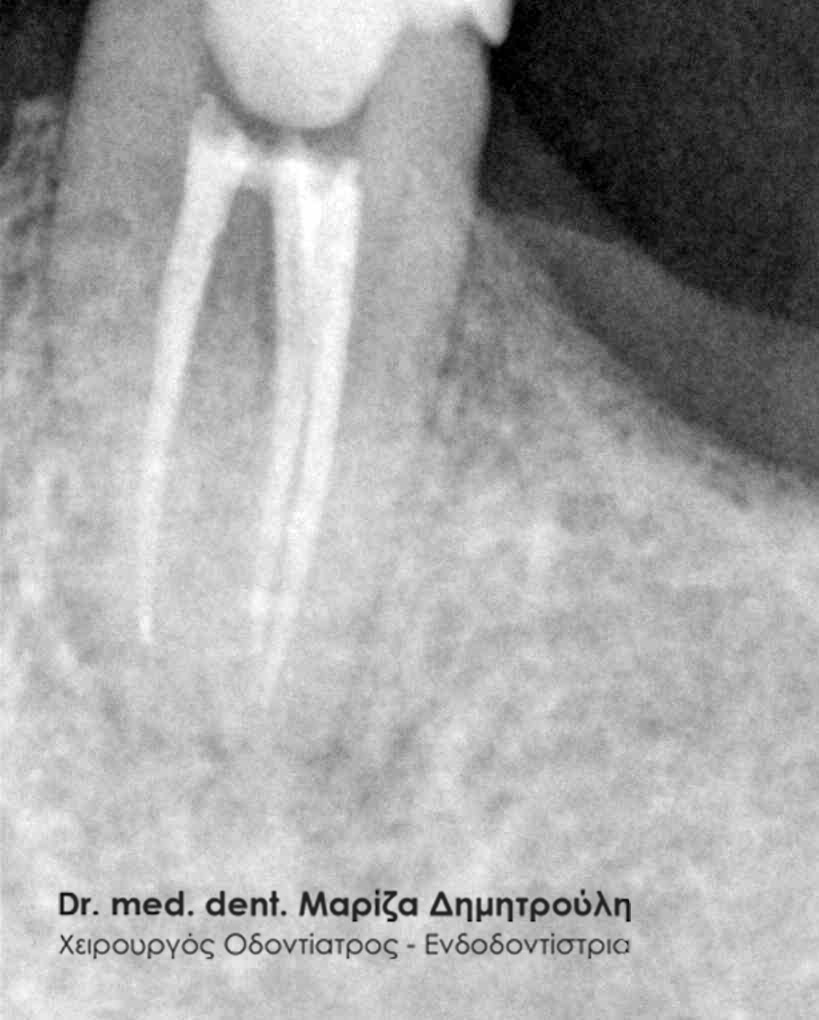

Στην περίπτωση αυτή ο ασθενής παραπέμπεται συνήθως στον ενδοδοντολόγο, με σκοπό να ξεκινήσει την επανάληψη της απονεύρωσης. Αυτό σημαίνει ότι ο ενδοδοντιστής θα αφαιρέσει μέσα από τις ρίζες του δοντιού την “παλιά απονεύρωση” ( δηλαδή το υλικό με το οποίο είχαν “γεμίσει” παλιά οι ριζικοί σωλήνες του δοντιού ), θα επεξεργαστεί και θα καθαρίσει εκ νέου τους ριζικούς σωλήνες του δοντιού. Εφόσον το δόντι παραμένει ασυμπτωματικό, η θεραπεία θα ολοκληρωθεί με την έμφραξη τόσο των ριζικών σωλήνων ( με γουταπέρκα, δηλαδή το υλικό με το οποίο εμφράσσονται οι ρίζες των δοντιών κατά την απονεύρωση ) όσο και της μύλης του δοντιού ( με λευκό σφράγισμα ).

Επανάληψη απονεύρωσης δοντιού

Τα ποσοστά επιτυχίας μιας απονεύρωσης δοντιού, στη σύγχρονη πλέον οδοντιατρική, κυμαίνονται στο 90-95 %. Υπάρχουν και κάποιες περιπτώσεις δοντιών, τα οποία μπορούν να εμφανίσουν αποτυχία της ενδοδοντικής θεραπείας. Δόντια με αποτυχημένη απονεύρωση με λίγα λόγια, είναι δόντια που έχουν απονευρωθεί και παρόλ΄ αυτά εμφανίζουν συμπτώματα πόνου. Τα συμπτώματα αυτά μπορεί να είναι